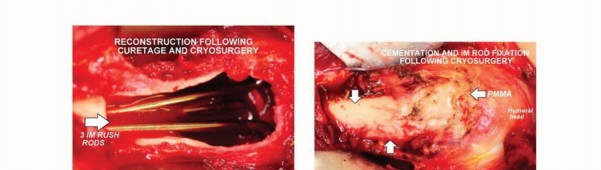

الكشط والعلاج المساعد (Curettage and Adjuvant Therapy):

تُستخدم عادة لأورام العظام الحميدة، حيث يتم كشط الورم من داخل العظم، ثم يتم استخدام مواد مساعدة مثل الفينول أو النيتروجين السائل أو الكي الكهربائي لتدمير أي خلايا ورمية متبقية.

5. العلاج بالتبريد (Cryoablation): النهج الثوري

يُعد العلاج بالتبريد، خاصةً بتقنية الصب المباشر بالنيتروجين السائل، ثورة حقيقية في علاج أورام العظام، حيث يقدم بديلاً فعالاً وآمنًا للجراحات الكبرى، مع الحفاظ على الطرف المصاب ووظيفته. يعتمد هذا النهج على تدمير الخلايا السرطانية عن طريق تعريضها لدرجات حرارة منخفضة جدًا، مما يؤدي إلى تجميدها وموتها.

تقنية الصب المباشر بالنيتروجين السائل: تفاصيل الإجراء

تعتبر تقنية الصب المباشر بالنيتروجين السائل (Direct Pouring Liquid Nitrogen Technique) في العلاج بالتبريد لأورام العظام من التقنيات المتقدمة التي تتطلب دقة عالية وخبرة جراحية متخصصة. يفضل الأستاذ الدكتور محمد هطيف هذه التقنية نظرًا لفعاليتها في تحقيق تجميد عميق وشامل للورم، مع الحفاظ على الأنسجة السليمة المحيطة.